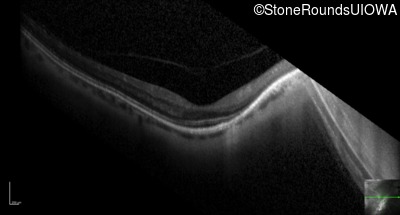

Optical Coherence Tomography - Right - 20/40 +2

Exemplar / OCT Stack